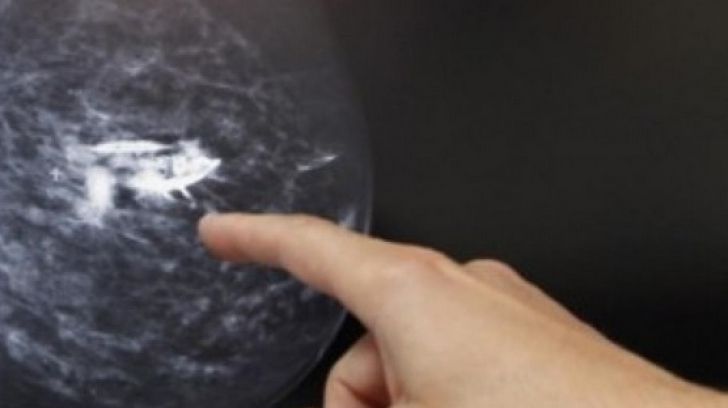

Medicul i-a indicat să facă o mamografie şi un examen medical cu ultrasunete. După câteva investigaţii amănunţite, acesta a constatat că femeia are cancer de sân localizat în ţesuturile profunde ale glandei mamare. Aceste adâncituri subtile au fost singurul semn vizibil de cancer.

"Aceste trei adâncituri, foarte, foarte discrete în partea de jos a sânului sunt, de fapt, un cancer de sân. Aşa arată cancerul meu de sân. Nu am simţit niciun nodul. Doctorul nu a palpat noduli", a scris femeia.

Mamologul australian Sue Fraser a declarat că adânciturile de acest fel la sân nu reprezintă un semn atât de specific în cancerul de sân ca depistarea unor noduli, însă pot fi un semn de cancer mamar, scrie unica.md.